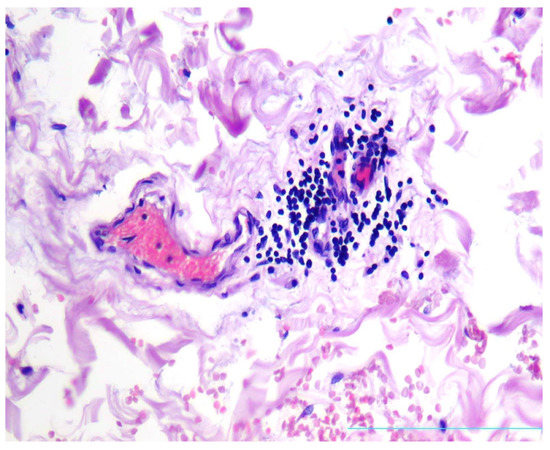

Condition “Vasa Vasorum” in Patients with Thoracic Aortic Aneurysm

by Petr V. Chumachenko, Alexandra G. Ivanova, Mariam Bagheri Ekta, Andrey V. Omelchenko, Vasily N. Sukhorukov, Alexander M. Markin, Yuliya V. Markina and Anton Y. Postnov

J. Clin. Med. 2023, 12(10), 3578; https://doi.org/10.3390/jcm12103578 - 20 May 2023

It is known that vasa vasorum contributes substantially to the blood supply and nutrition of one-third of the wall of the ascending thoracic aorta. Therefore, we focused on studying the relationship between inflammatory cells and vasa vasorum vessels in patients with aortic aneurysm. [...] Read more.

It is known that vasa vasorum contributes substantially to the blood supply and nutrition of one-third of the wall of the ascending thoracic aorta. Therefore, we focused on studying the relationship between inflammatory cells and vasa vasorum vessels in patients with aortic aneurysm. The material for the study was biopsies of thoracic aortic aneurysms taken from patients during an aneurysmectomy (34 men, 14 women, aged 33 to 79 years). The biopsies belonged to patients with non-hereditary thoracic aortic aneurysm. An immunohistochemical study was carried out using antibodies to antigens of T cells (CD3, CD4, CD8); macrophages (CD68); B cells (CD20); endothelium (CD31, CD34, von Willebrand factor (vWF)); and smooth muscle cells (alpha actin). Samples without inflammatory infiltrates contained less vasa vasorum in the tunica adventitia than samples with inflammatory infiltrates, and this difference was statistically significant p < 0.05. T cell infiltrates in the adventitia of aortic aneurysms were found in 28 of 48 patients. In the vessels of the vasa vasorum, surrounded by inflammatory infiltrates, T cells that adhered to the endothelium were found. The same cells were also localized in the subendothelial area. The number of adherent T cells in patients with inflammatory infiltrates in the aortic wall dominated the number of these cells in patients without inflammation of the aortic wall. This difference was statistically significant, p < 0.0006. Hypertrophy and sclerosis of the arteries of the vasa vasorum system, the narrowing of their lumen, and, as a result, impaired blood supply to the aortic wall, were found in 34 patients with hypertension. In 18 patients (both in patients with hypertension and in patients without hypertension), T cells that adhered to the vasa vasorum endothelium were found. In nine cases, massive infiltrates of T cells and macrophages were found, which surrounded and squeezed the vasa vasorum, preventing blood circulation. In six patients, parietal and obturating blood clots were found in the vasa vasorum vessels, which disrupted the normal blood supply to the aortic wall. We believe that this indicates the importance of the state of the vessels of the vasa vasorum in the development of an aortic aneurysm. In addition, pathological changes in these vessels may not always play a primary role, but always a very important role, in the pathogenesis of this disease. Full article